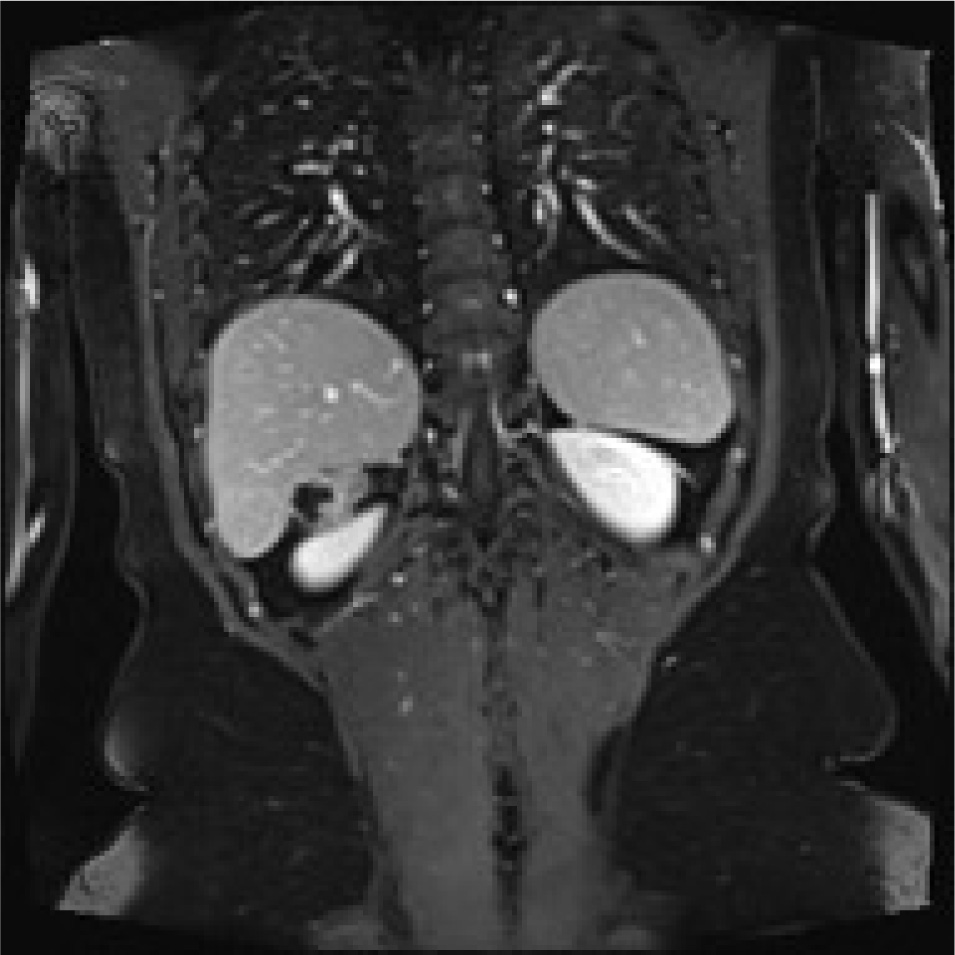

A 78-years old Moroccan woman was admitted to our department for a right flank pain without any other relevant symptoms or signs; she referred to only a light pain radiating to the epigastric region. The pain had started eight or ten months previously, she had no nausea or vomiting, she was afebrile and her vital signs were normal. She denied any contact with dogs or sheep and she had moved from Morocco to Italy in 2009. She was unemployed. Her physical examination was normal, without any significant signs or symptoms, which could suggest retroperitoneal abdominal masses. When she was a child she had the common infective diseases and at the moment of physical examination she had only an iron deficiency anemia. She underwent two Caesarean Births in 2009 and 2012. We performed routine laboratory exams on her, such as hemocromocitometric panel, major biochemical values and principal enzymes; there was no pathological alteration. She underwent ultrasound abdominal exam so we found a strange ovoidal hypoechoic formation in the right adrenal gland space; it was four centimetres in maximum diameter, and there were no signs of peripheral or central vascularization at Doppler’s exam; it was impossible to establish a sure diagnosis so we proposed a CT scan of the abdomen. The CT scan showed a solid mass of maximum diameter 5 cm, with a light peripheral vascularization and degenerative cystic areas; it had no clear linkage with either liver or with right adrenal gland. Therefore we decided to admit her to perform other imaging and laboratory exams; in fact we required an abdominal MRI which showed: “mass of 34 x 27 mm with a central cyst composed of a multilocular structure, there are signs of parietal vascularization and there aren’t signs of a clear dissection plane from kidney and liver”(image 1,2,3,4). Despite this we continued with a screening exam for HD such as indirect hemaglutination test and also hormonal exams both for adrenal cortex hormones and medullar catecholamines; all these exams were negative. We decided to perform a surgical approach to this mass, because we had to have a sure histological diagnosis of the mass; we gained the informed consent for surgical procedure. We set up the patient on the operating table in lateral left decubitus, we obtained a pneumoperitoneum with open technique and after an accurate exploration of abdominal cavity placed another three trocars to complete the procedure. We gained access to the retroperitoneal space with the same surgical steps of a laparoscopic adrenalectomy. There were significant adhesions between the unknown mass and the liver, kidney and adrenal gland. The mass was removed after a dissection through an unclear plane between liver and lesion. We extracted it into a laparoscopic bag from the access in right flank (image 5). The postoperative course was regular, without relevant complications. Unfortunately the definitive histological report was unclear. There was a significant rise in IG indirect hemagglutination one month after the surgical procedure (Indirect Haemoagglutination Assay was 1:600). Therefore we called a specialist for expert advice and finally we reached a conclusive diagnosis: Hydatid cyst localized in the retroperitoneal right adrenal gland space. Now the patient is in good health; even so, we have prescribed her a prophylactic drug treatment with albendazole.

Rm scan T2 weighted coronal image showing the adrenal mass